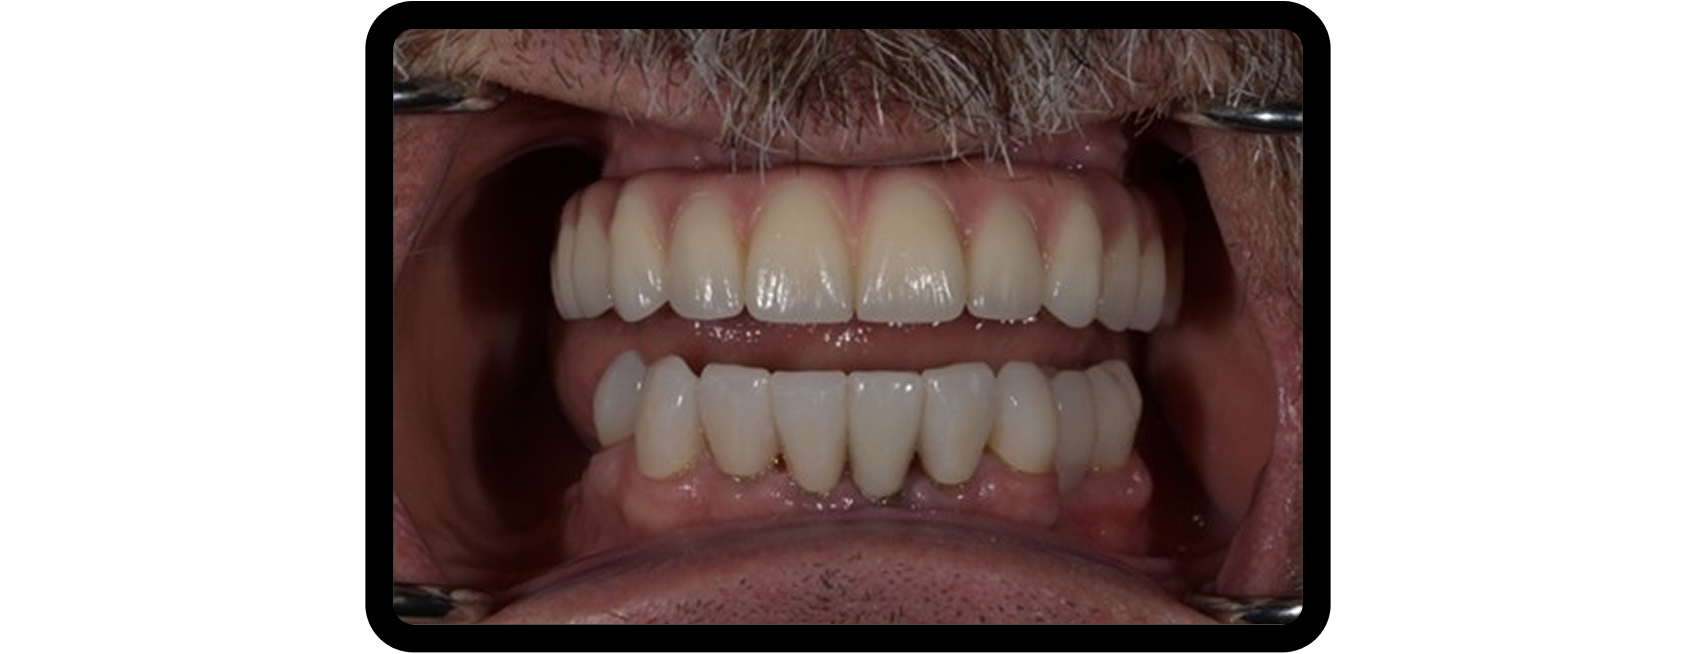

After radiographic analysis, periodontal assessment, and occlusal examination, Jerry presented with failing maxillary dentition supported by a removable partial denture, significant occlusal collapse, and esthetic dissatisfaction, all of which negatively affected his confidence at work (Fig. 1).

His occlusal collapse included uneven wear and super-eruption of the left maxillary cuspid, contributing to his functional and esthetic concerns (Fig. 2).

The maxillary arch was restored first, followed by mandibular rehabilitation (Fig. 6) and provisionalization at the new VDO to allow patient adaptation and functional evaluation (Fig. 7).